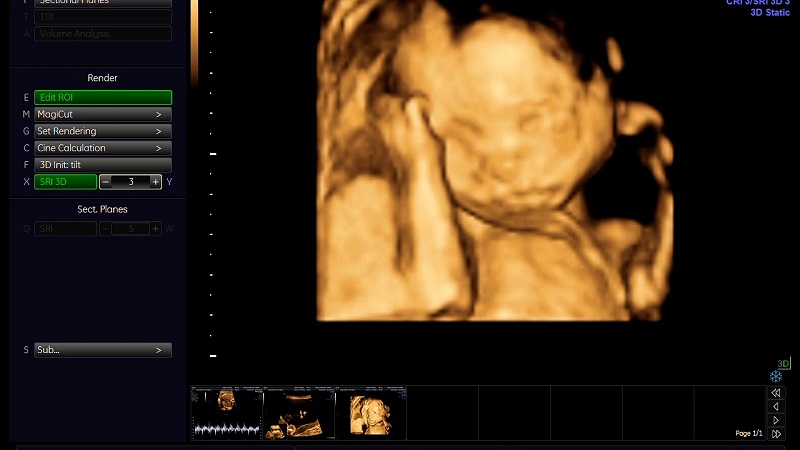

Công nghệ siêu âm vô cùng hữu ích khi giúp bác sĩ lẫn mẹ bầu nhìn thấy được hình ảnh, chuyển động lẫn sự phát triển của thai nhi trong bụng mẹ. Siêu âm hoạt động dựa trên nguyên lý sóng âm có tần số cao, vượt qua ngưỡng thính giác của chúng ta có thể nghe thấy được. Khi đầu dò siêu âm phát ra những sóng âm này tiếp xúc với thành bụng của mẹ bầu, chúng xuyên qua da và phản xạ trở lại dưới dạng hình ảnh chi tiết của thai nhi đang phát triển.

Bác sĩ dùng đầu dò di chuyển trên thành bụng thai phụ để truyền về hình ảnh thai nhi trong bụng. Siêu âm vùng bụng hiện nay có rất nhiều loại, bao gồm: